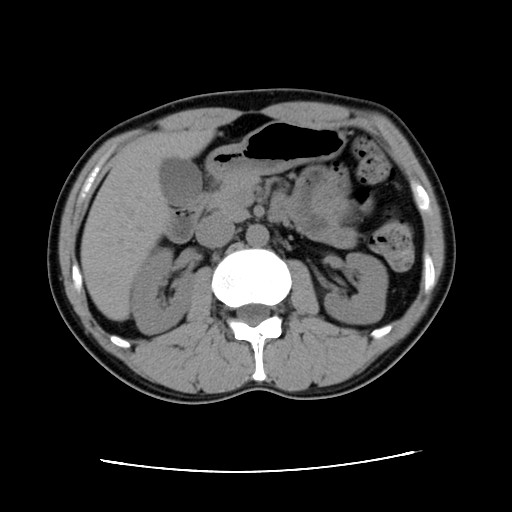

ちなみに2006/11/1。

脂肪がないw